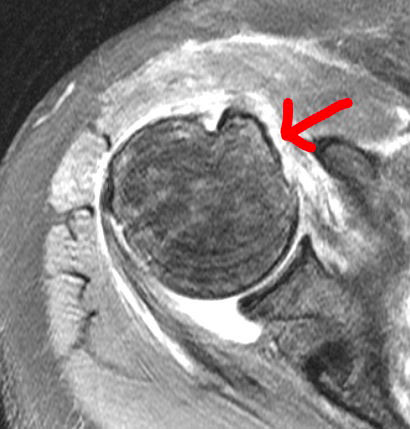

Subscapularis Tendon Tear

Subscapularis tendon tear is on the left with the healed repair visible on the right.